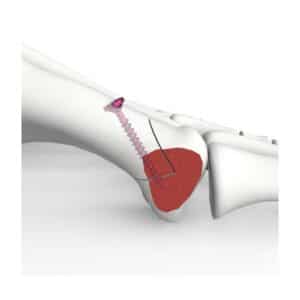

SISTEMA DE ARTROPLASTIA ANATOMICA DE LIGAMENTOS DEL PULGAR (ATLAS)

La técnica ATLAS está destinada a corregir la inestabilidad CMC del pulgar y facilitar un rápido retorno a la función mediante la colocación de fijaciones estables de anclaje basado en suturas en los sitios anatómicos de inserción del ligamento basal del pulgar.